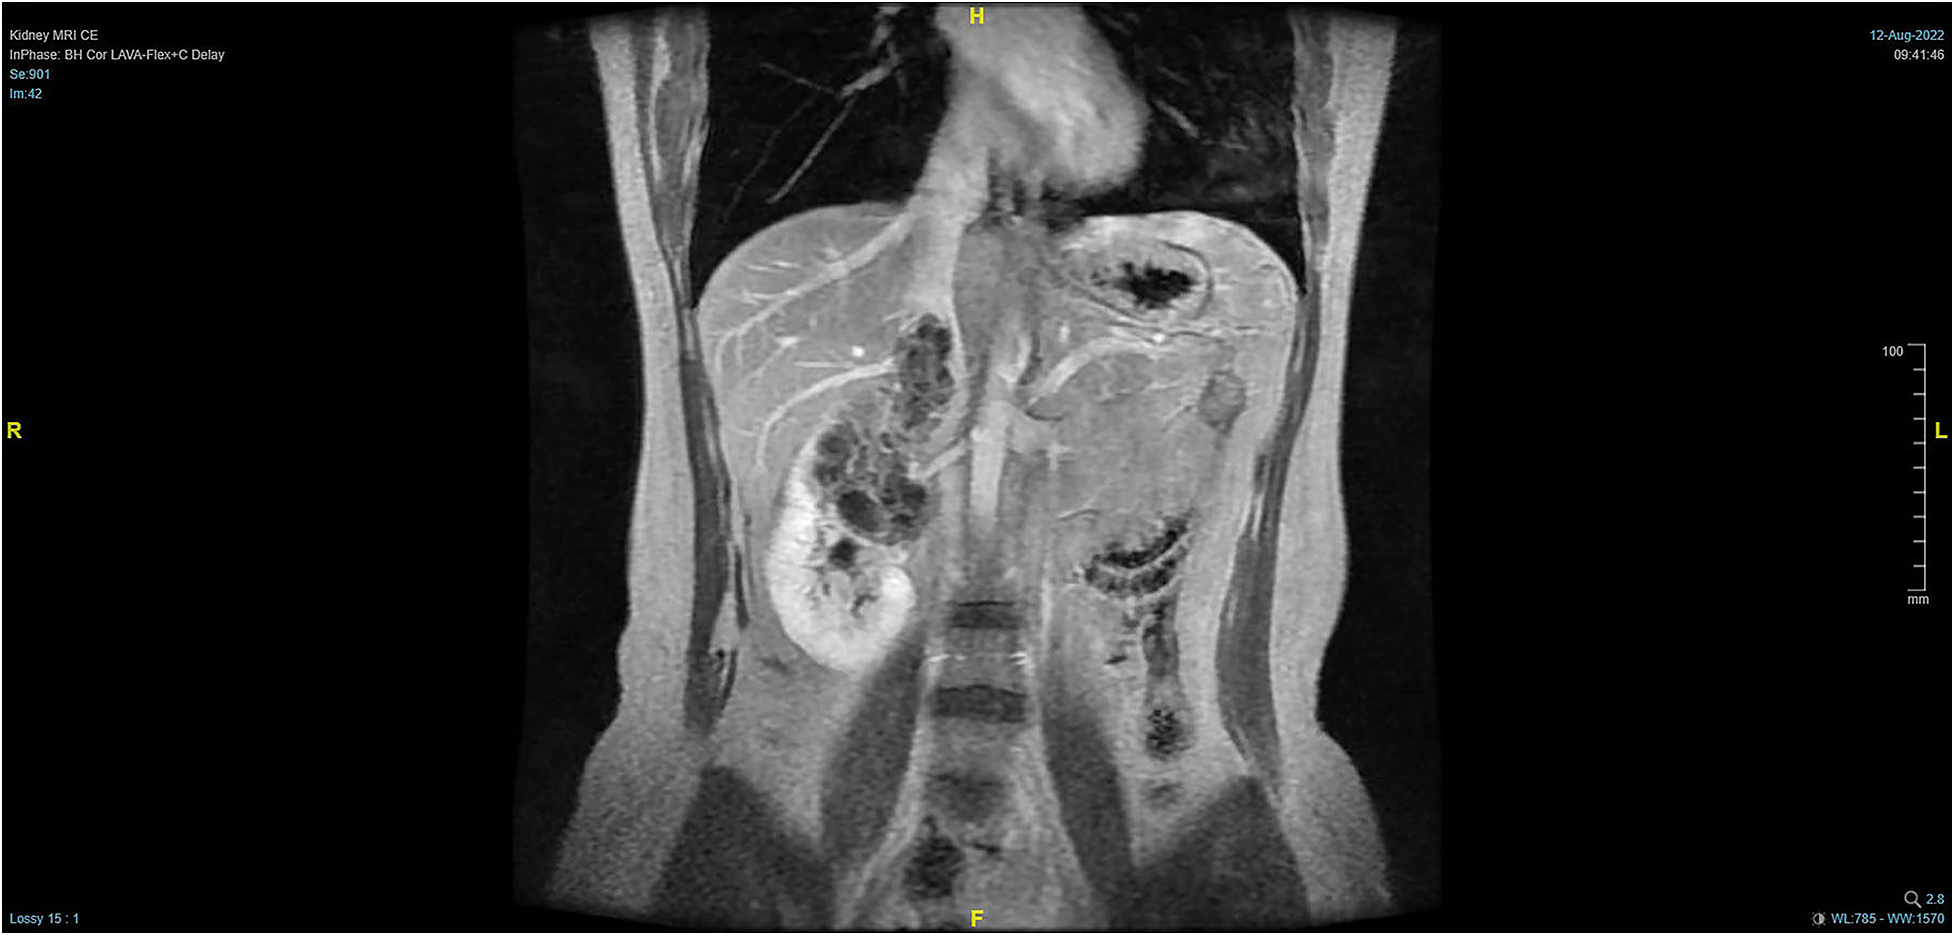

Figure 1

Pre-operative MRI showing that the tumor lesion enlarged upward along the right renal vein into the inferior vena cava (coronal planes).

The patient, a 38-year-old woman, was admitted to the hospital after a physical examination revealed right renal space-occupying lesion for one week. She had no other medical, personal, or family history, other than a history of hamartoma. After admission, the patient underwent the MRI of both kidneys, which revealed an irregularly shaped mass at the upper pole of the right kidney. This mass was characterized by equally short T1 weighted image (T1WI) and T2WI signals, and the signals in the fat-suppression image were not significantly reduced. Multiple cystic components were seen in the mass, some of which were filled with fluid, and the lesion spread into the renal sinus and upward to the inferior vena cava. The right renal veins were not clearly visible. The maximum cross-sectional area of the lesion was about 10.4 × 5.5 cm (coronal). The enhancement scan showed heterogeneity, marked enhancement, separated enhancement, and local clear contour in the delay period. The right kidney was occupied, with multiple cystic variations and hemorrhages in the lesion, and it spread upward along the right renal vein into the inferior vena cava. Malignancy was not ruled out (Figures 1, 2). Urological CT of both kidneys indicated that the right kidney had a space-occupying lesion and that the size and shape of both kidneys were normal.